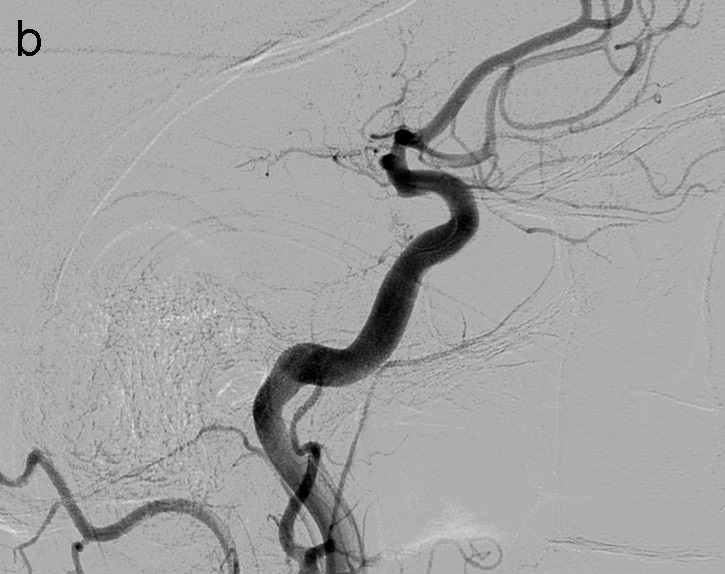

La técnica SAVE consiste en combinar stentriever (colocándolo con el trombo en su tercio proximal) y un catéter de aspiración (en contacto con la porción proximal del trombo) y realizar el pase actuando como una unidad, ofreciendo una captura distal (stentreiver) y proximal del coágulo con el catéter de aspiración (imagen 4). Se retiran simultáneamente bajo aspiración con bomba y manual a través del catéter balón.

Se vuelve a realizar una serie a través del FlowGate2, en este caso demostrando una apertura completa de la ACM y sus ramas hemisféricas derechas, TICI 3 (imagen 5).